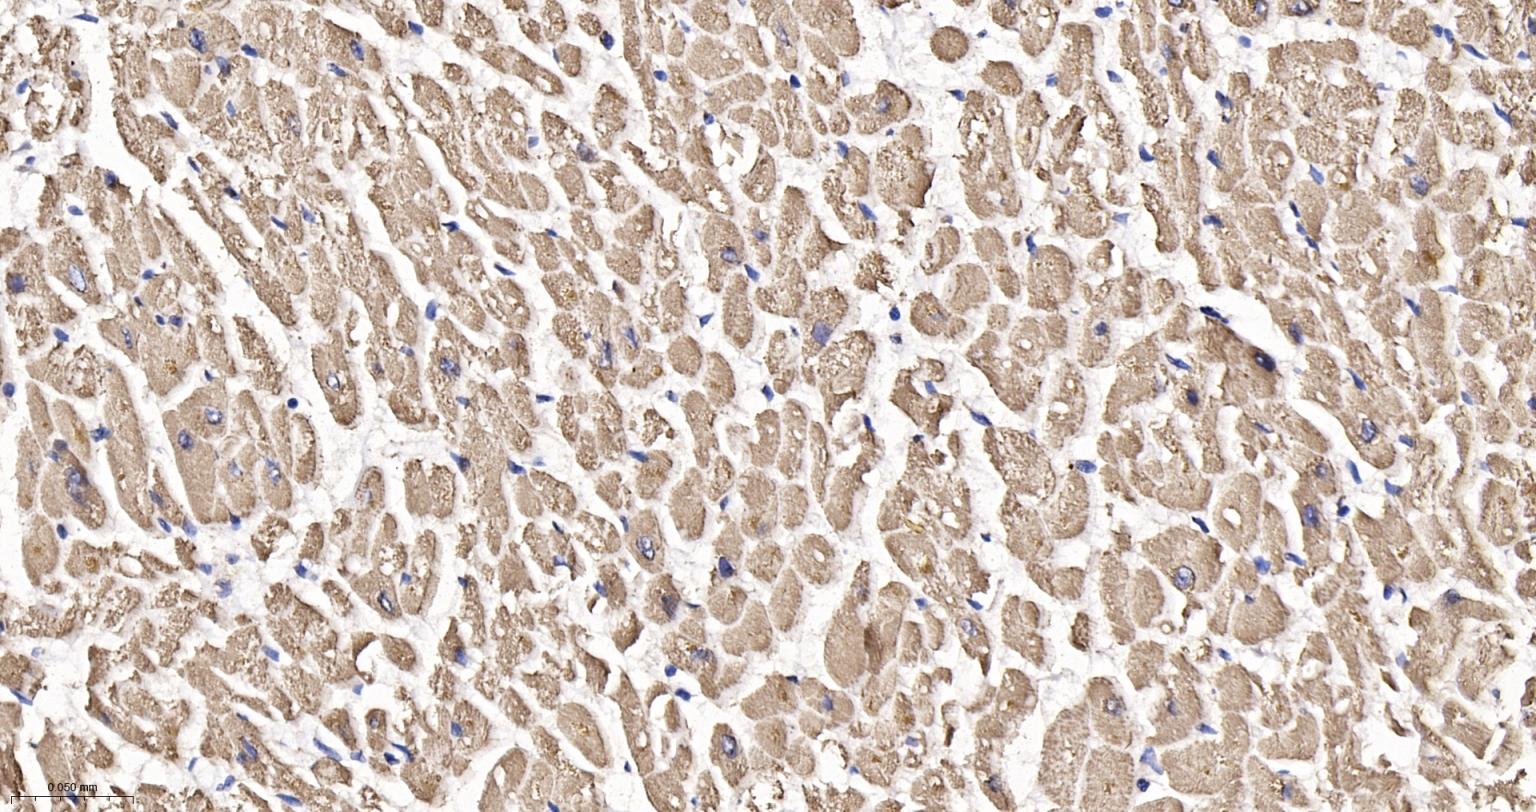

Paraformaldehyde-fixed, paraffin embedded Human Heart; Antigen retrieval by boiling in sodium citrate buffer (pH6.0) for 15 min; Antibody incubation with ATPB Monoclonal Antibody, Unconjugated(bsm-52904R) at 1:200 overnight at 4°C, followed by conjugation to the bs-0295G-HRP and DAB (C-0010) staining.